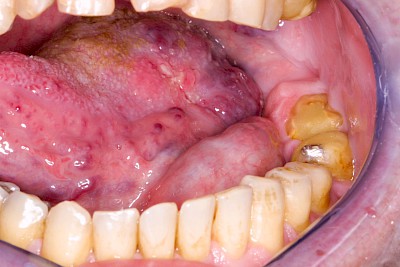

Rötung, Blutung, Verletzung

Gaumen, Wange & Zunge

Rötungen sind grundsätzlich als Anzeichen einer Entzündung zu werten.

Die 5 klassischen Entzündungszeichen:

- Rötung (Rubor)

- Schmerzen (Dolor)

- Schwellung (Tumor)

- Wärme (Calor)

- gestörte Funktion (Functio laesa)

Kauen auf Wange, Zunge & Lippen

Das Kauen auf Wange, Zunge oder Lippen zählt zu den sogenannten Habits und ist meist stressbedingt. Diskrete Linien (Verhornungsleisten) oder aber unruhige Schleimhautareale bis hin zu Erscheinungsformen wie "wildes Fleisch" können dabei auffallen.

Beispiele32 Bilder